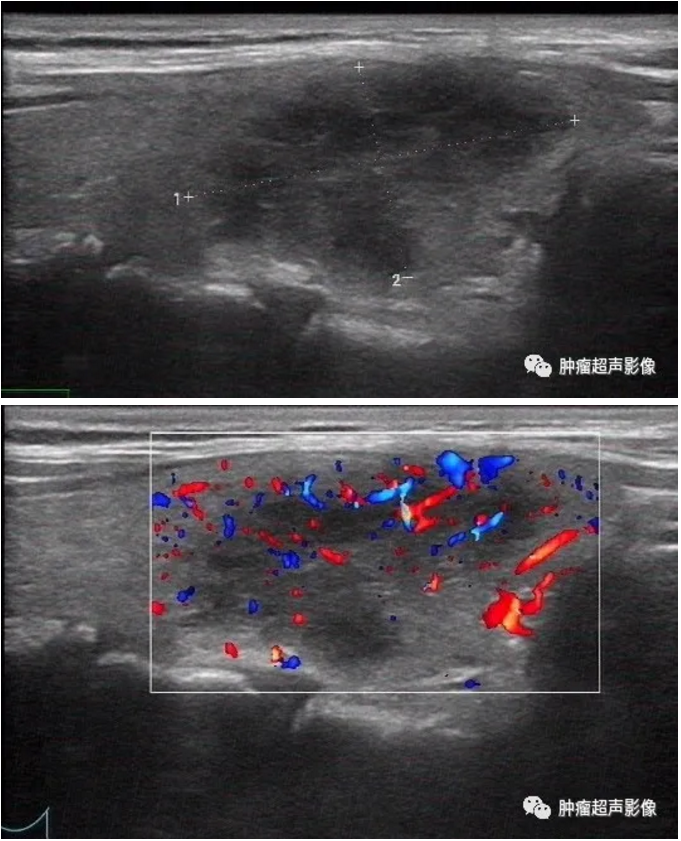

请继续看下面1个月、3个月后超声复查图像

与上面同一个病例1月后复查:

左图:甲状腺右叶低回声,一个月后复查显示变化明显

右图:1月前正常甲状腺左叶出现两个低回声

同一个病例2月后继续复查:

左图:甲状腺右叶低回声,两个月后复查显示缩小明显

右图:甲状腺左叶低回声明显变大。

(因为左右叶明显反转变化,医师及患者有可能认为你报告写反了,还会过来质疑,此情况恰恰说明了亚甲炎图像短期变化明显,符合亚甲炎的诊断)